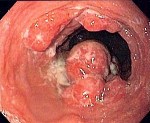

Диагноз выставляется с учетом анамнеза, жалоб, данных объективного осмотра, результатов инструментальных и лабораторных исследований. При опросе обращают внимание на прогрессирование пострезекционных жалоб в динамике, отсутствие аппетита, снижение веса и появление «желудочного дискомфорта». Наиболее информативным методом исследования, позволяющим достоверно диагностировать рецидив рака желудка, является гастроскопия с эндоскопической биопсией. Для выявления асцитической жидкости и метастазов в печени назначают УЗИ органов брюшной полости. В некоторых случаях при использовании этой методики также удается обнаружить увеличенные забрюшинные лимфатические узлы.